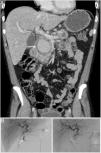

La pancreatitis aguda es una patología común y potencialmente grave que tiene un curso clínico muy variable. Este artículo pretende revisar el papel de las distintas técnicas de imagen en el manejo de esta entidad, describir sus principales manifestaciones radiológicas y la nomenclatura específica asociada a esta entidad.

Acute pancreatitis is common; the clinical course of this potentially severe condition varies widely. This paper aims to review the role of different imaging techniques in the management of acute pancreatitis, describe the main imaging findings for this entity, and explain the terms and criteria used to classify them.